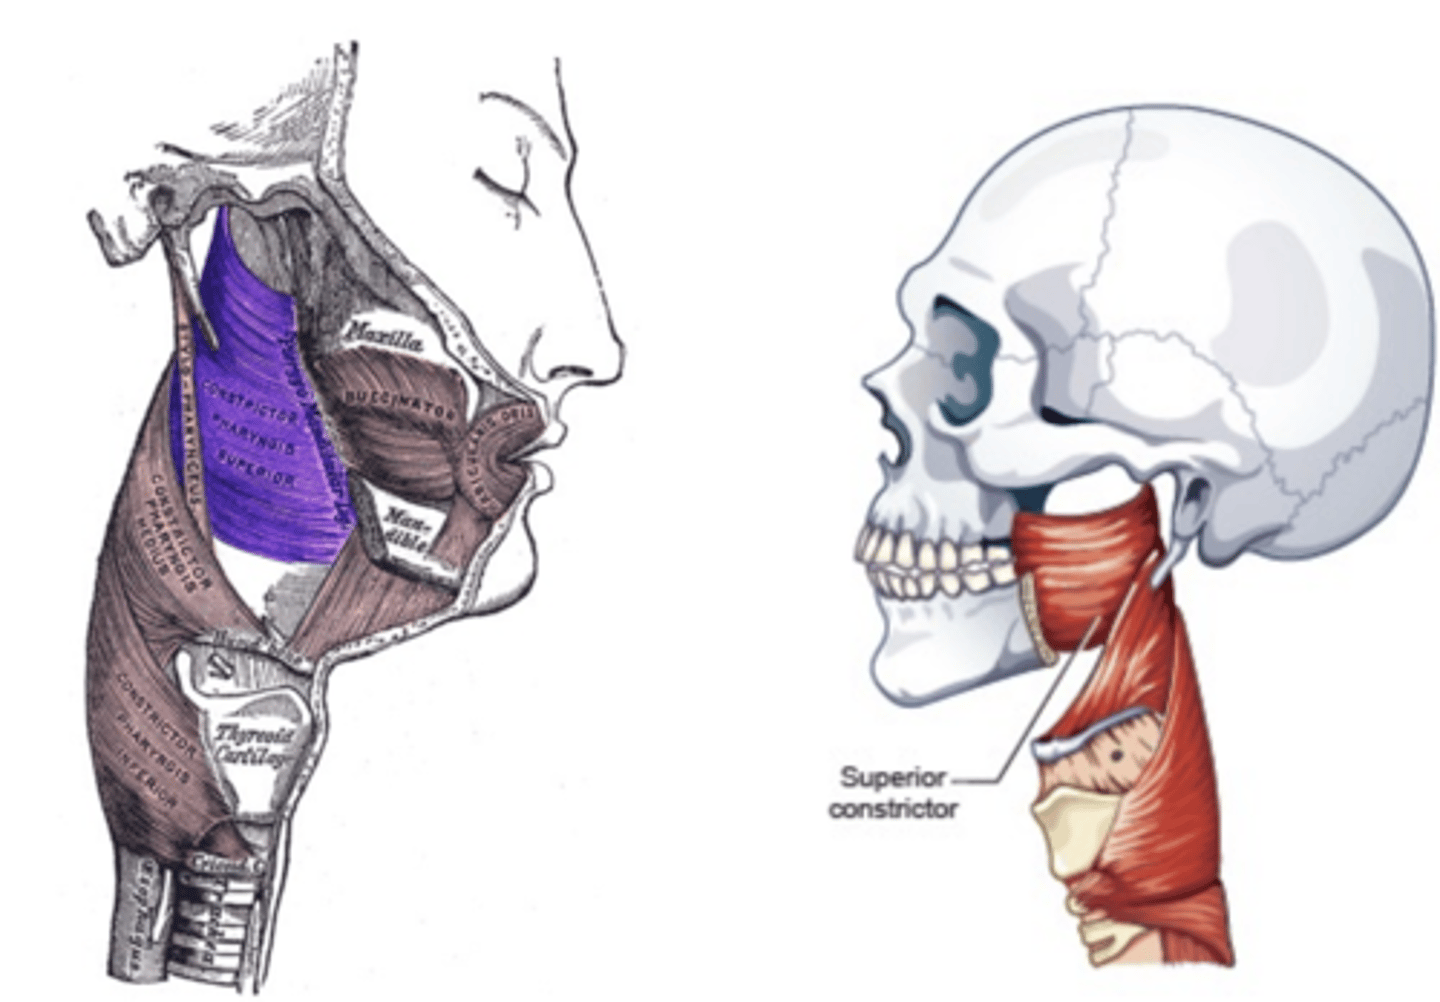

Superior Constrictor Figure

Middle Constrictor Figure

Thyropharyngeus Figure

Cricopharyngeus Figure

Stylopharyngeus Figure

Salpingopharyngeus Figure

Palatopharyngeus Figure

3 pairs of muscles, referred to as constrictors

Action of each is to reduce the diameter of a portion of the pharyngeal cavity

Constrictor Muscle Actions

Constrictor muscles all pull pharyngeal

walls inward and forward to constrict

the pharyngeal tube